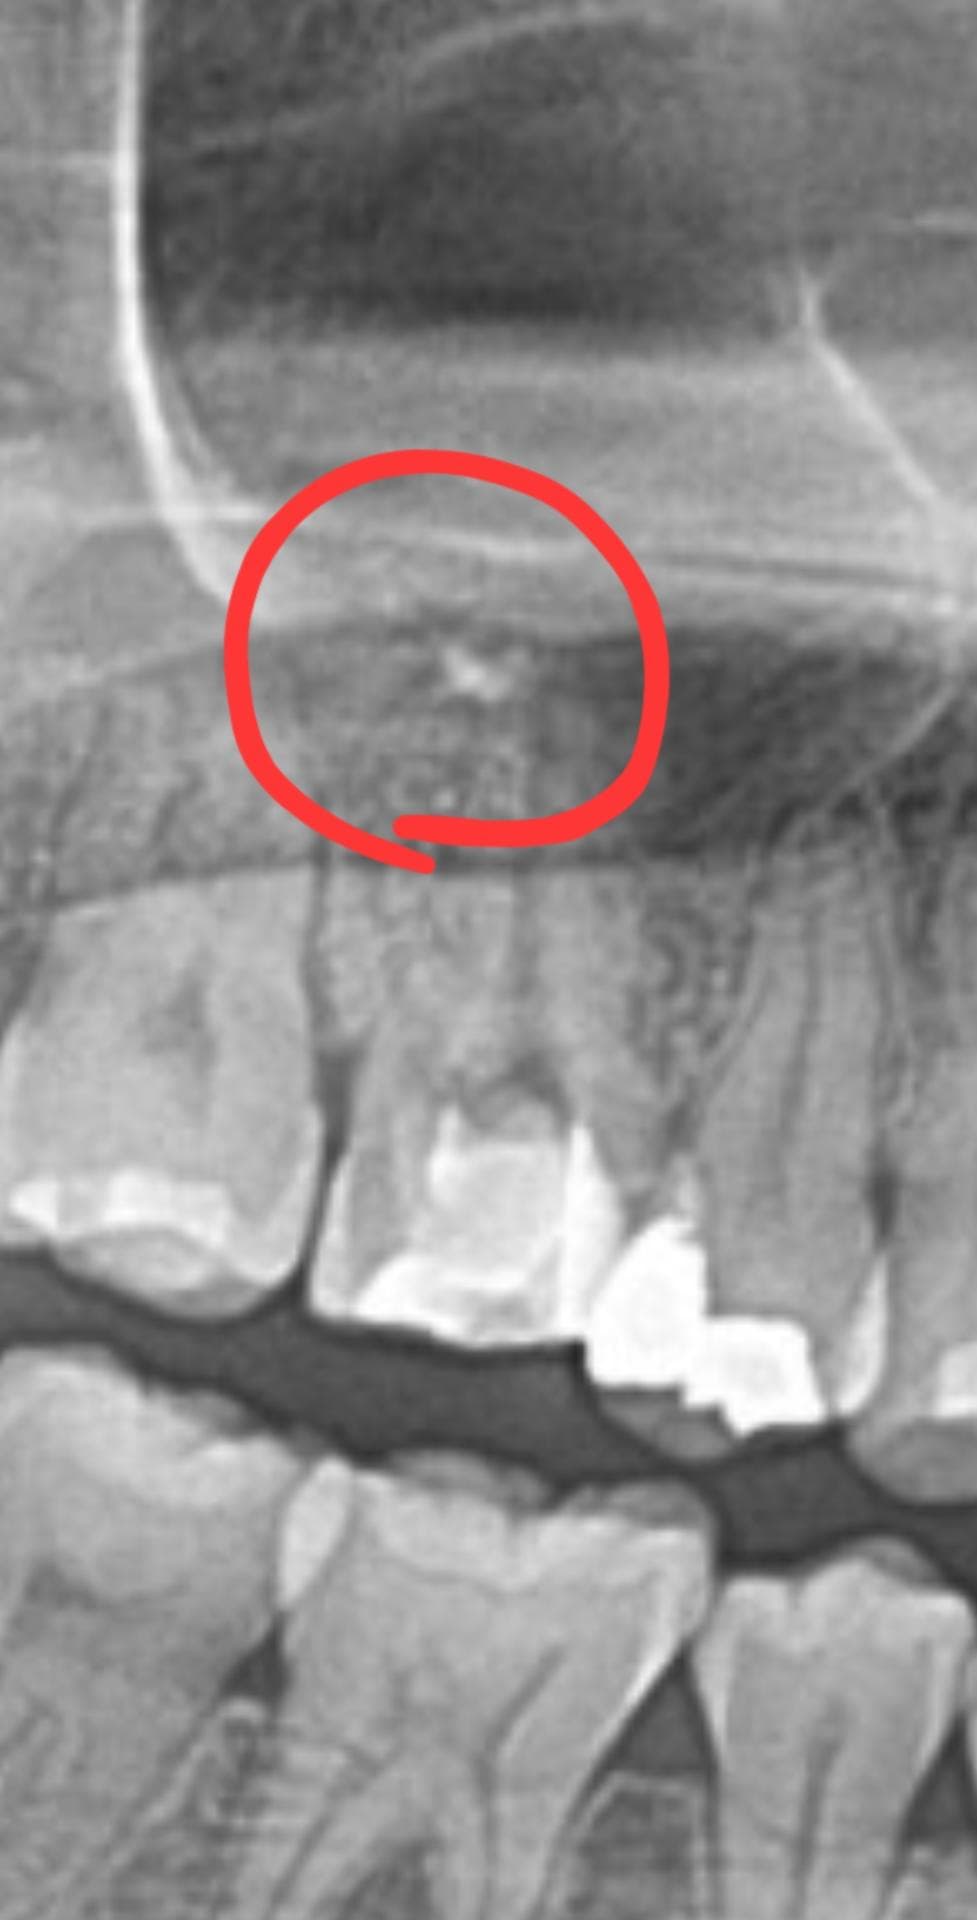

오늘 파노라마 사진 찍었는데,.저렇게 하얀색 점이 발견되었습니다.

혹시 과충전 된 걸까요??!

소독 2회 진행했는데, 2회차때 저렇게 생긴 것 같습니다.

현재 사진상 보이기로는 충전이 마무리된 상태가 아니고요 저건 최종 충전 물질이 아닙니다. 염증 상태 개선을 위해 첩약한 수산화 칼슘 재료가 좀 남아있는것 같습니다. 점차 흡수됩니다 걱정마세요

아직은 신경치료가 마무리가 안된거 같습니다. 약재가 살짝 넘어간경우는 발생할수 잇으며 크게 문제가 되진 않습니다.

사진으로 봤을 경우에는 충전이 되고 있는 상태가 아닌 것으로 보입니다. 신경치료를 할 때 재료가 치아 뿌리 끝을 넘어가는 과충전 증상이 있을 수 있지만 대부분 충전이 부족한 것보다는 예후가 좋은 경우가 많습니다.